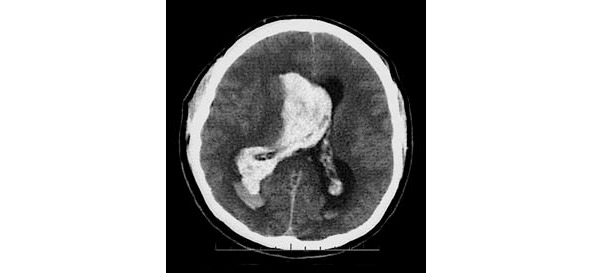

Среди геморрагических вариантов ОНМК выделяют: паренхиматозное кровоизлияние, вентрикулярное кровоизлияние, паренхиматозно-вентрикулярное кровоизлияние (рис. 3), а также субарахноидальное кровоизлияние.

Рисунок 3. КТ-картина паренхиматозно-вентрикулярного кровоизлияния